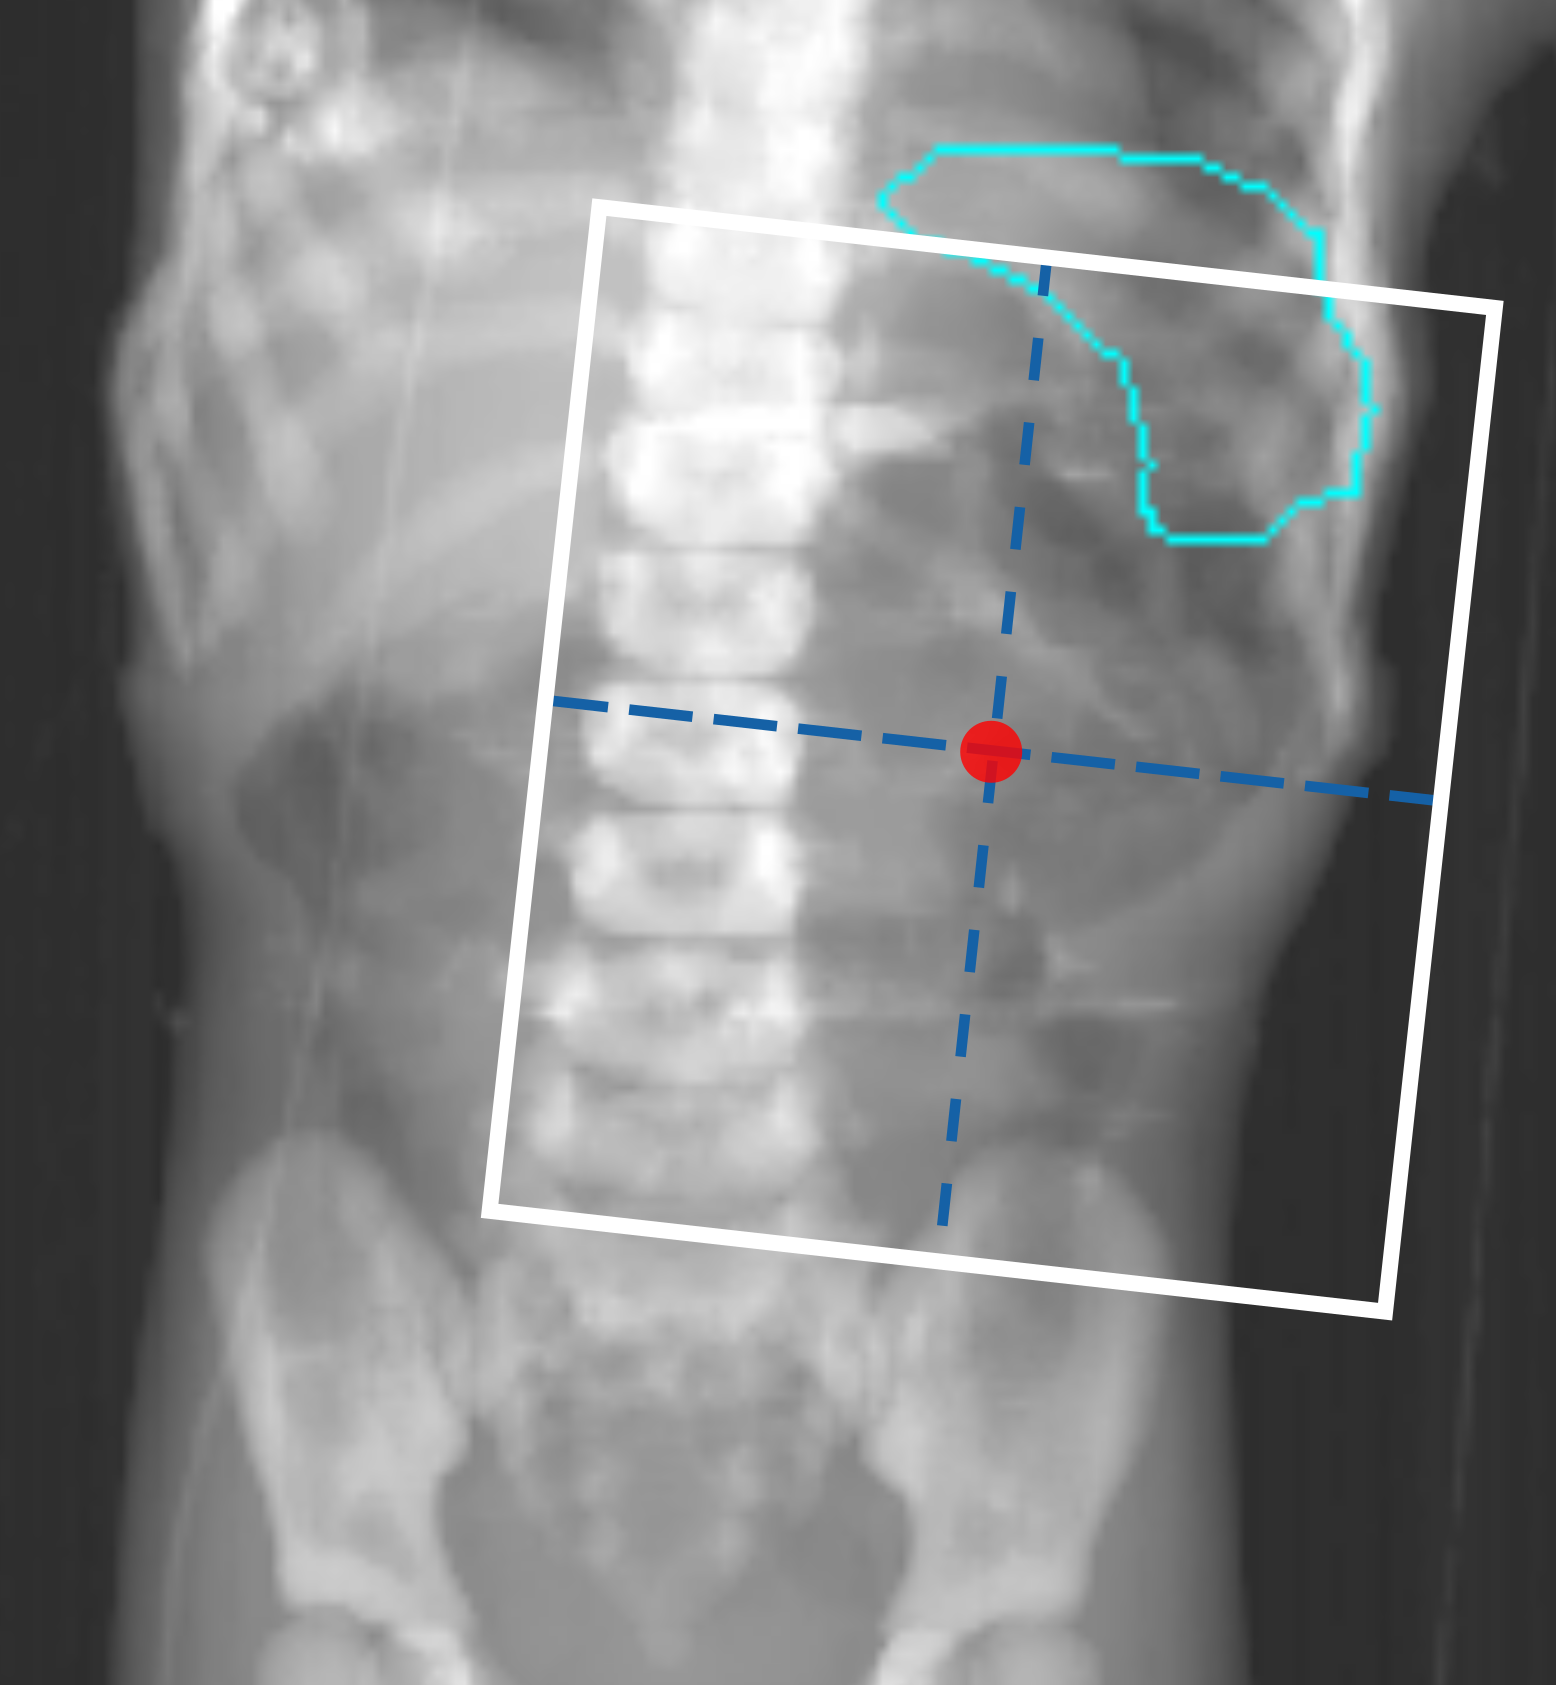

Figures 1(a) and 1(c) illustrate examples of actual historical plans on respective historical radiographs. As can be observed, a typical historical flank irradiation field is a rectangular area, with possible shielding blocks, that is located on the right or on the left flank. Irradiation is done by beams from anterior-posterior (AP) and posterior-anterior (PA) direction. Along right-left (RL), one field border is located at the edge of the patient’s body contour, while the other is located as to include the vertebral column (?). In some cases, blocks are placed to protect OARs from irradiation (Fig. 1(c)). In historical plans the isocenter is positioned in the center of the treatment field that is projected on the coronal plane (Fig. 1) and at the middle of the patient’s AP abdominal diameter.

To generate artificial plans, two reference digitally reconstructed radiographs (DRRs) were considered, randomly selected from the data. One DRR was derived from a CT of a 5-year old female patient without nephrectomy (ref 1 in Fig. 2), and the other was derived from a CT of a 4-year old female patient with nephrectomy of the left kidney (ref 2 in Fig. 2). Upon these two DRRs, boundaries defining the extent of variation for clinically reasonable fields were identified by an experienced pediatric radiation oncologist (B. V. Balgobind) Note that historical clinical guidelines are slightly different from current ones (e.g., currently the iliac crests should be safeguarded, unlike in Fig. 1(c)). Figure 2 shows two examples of landmark locations identifying possible plan variations, on the two reference DRRs. Specifically, given the boundaries of possible isocenter positions and field borders, plans with a rectangular field were generated by sampling uniformly within those boundaries.

For each plan generated, an additional version of that plan including one block was generated as well. A block was simulated as the area in the upper lateral corner enclosed by the border of the rectangular field and a line crossing two randomly sampled endpoints. The endpoints were sampled from two regions roughly covering the start and end points of rib 9 and rib 12 on the DRRs (regions indicated by the green boxes in Fig. 2). This way, a sampled block covered part of the liver (in right-sided plans) or part of the spleen (in left-sided plans). All plans consisted of two opposing and symmetrical beams in AP-PA directions irradiating one side of the abdominal flank. Figures 1(b) and 1(d) illustrate two examples of sampled artificial plans (without or with a block) on respective DRRs.